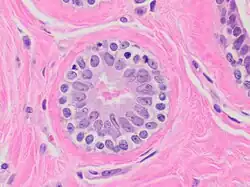

Acini séreux

• Cellule de forme pyramidale

• Lumière étroite

• noyau central arrondi

• Réticulum endoplasmique rugueux (RER) ou granuleux (REG) très développé, cytoplasme souvent basophile

• Présence de grain de sécrétion au pôle apical. Rejette son produit de sécrétion selon un mode mérocrine.

Exemple : acinus pancréatique